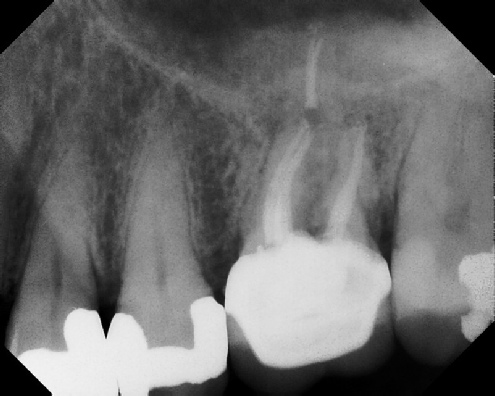

Root Canal Retreatment - Meriden 8 mos. recall Post-op Pre-op